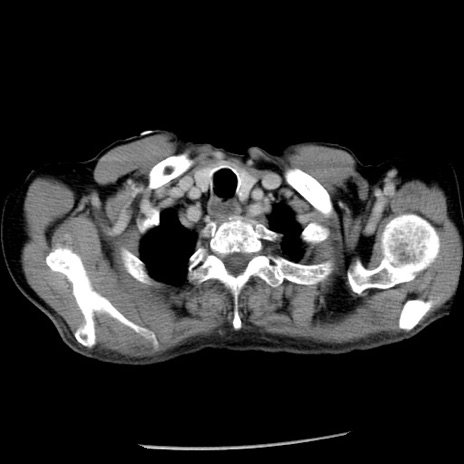

冠状断像

症例26(横断像)

【症例】80歳代男性

【主訴】嘔吐

【現病歴】昨晩2回嘔吐あり、今朝になっても嘔吐あり。来院。

【既往歴】胃潰瘍

【身体所見】意識清明、BT 37.6℃、BP 166/95mmHg、HR 100bpm、SpO2 97%、腹部:平坦・軟、腸蠕動音聴取良好、圧痛なし。

【データ】WBC 21900、CRP 1.46